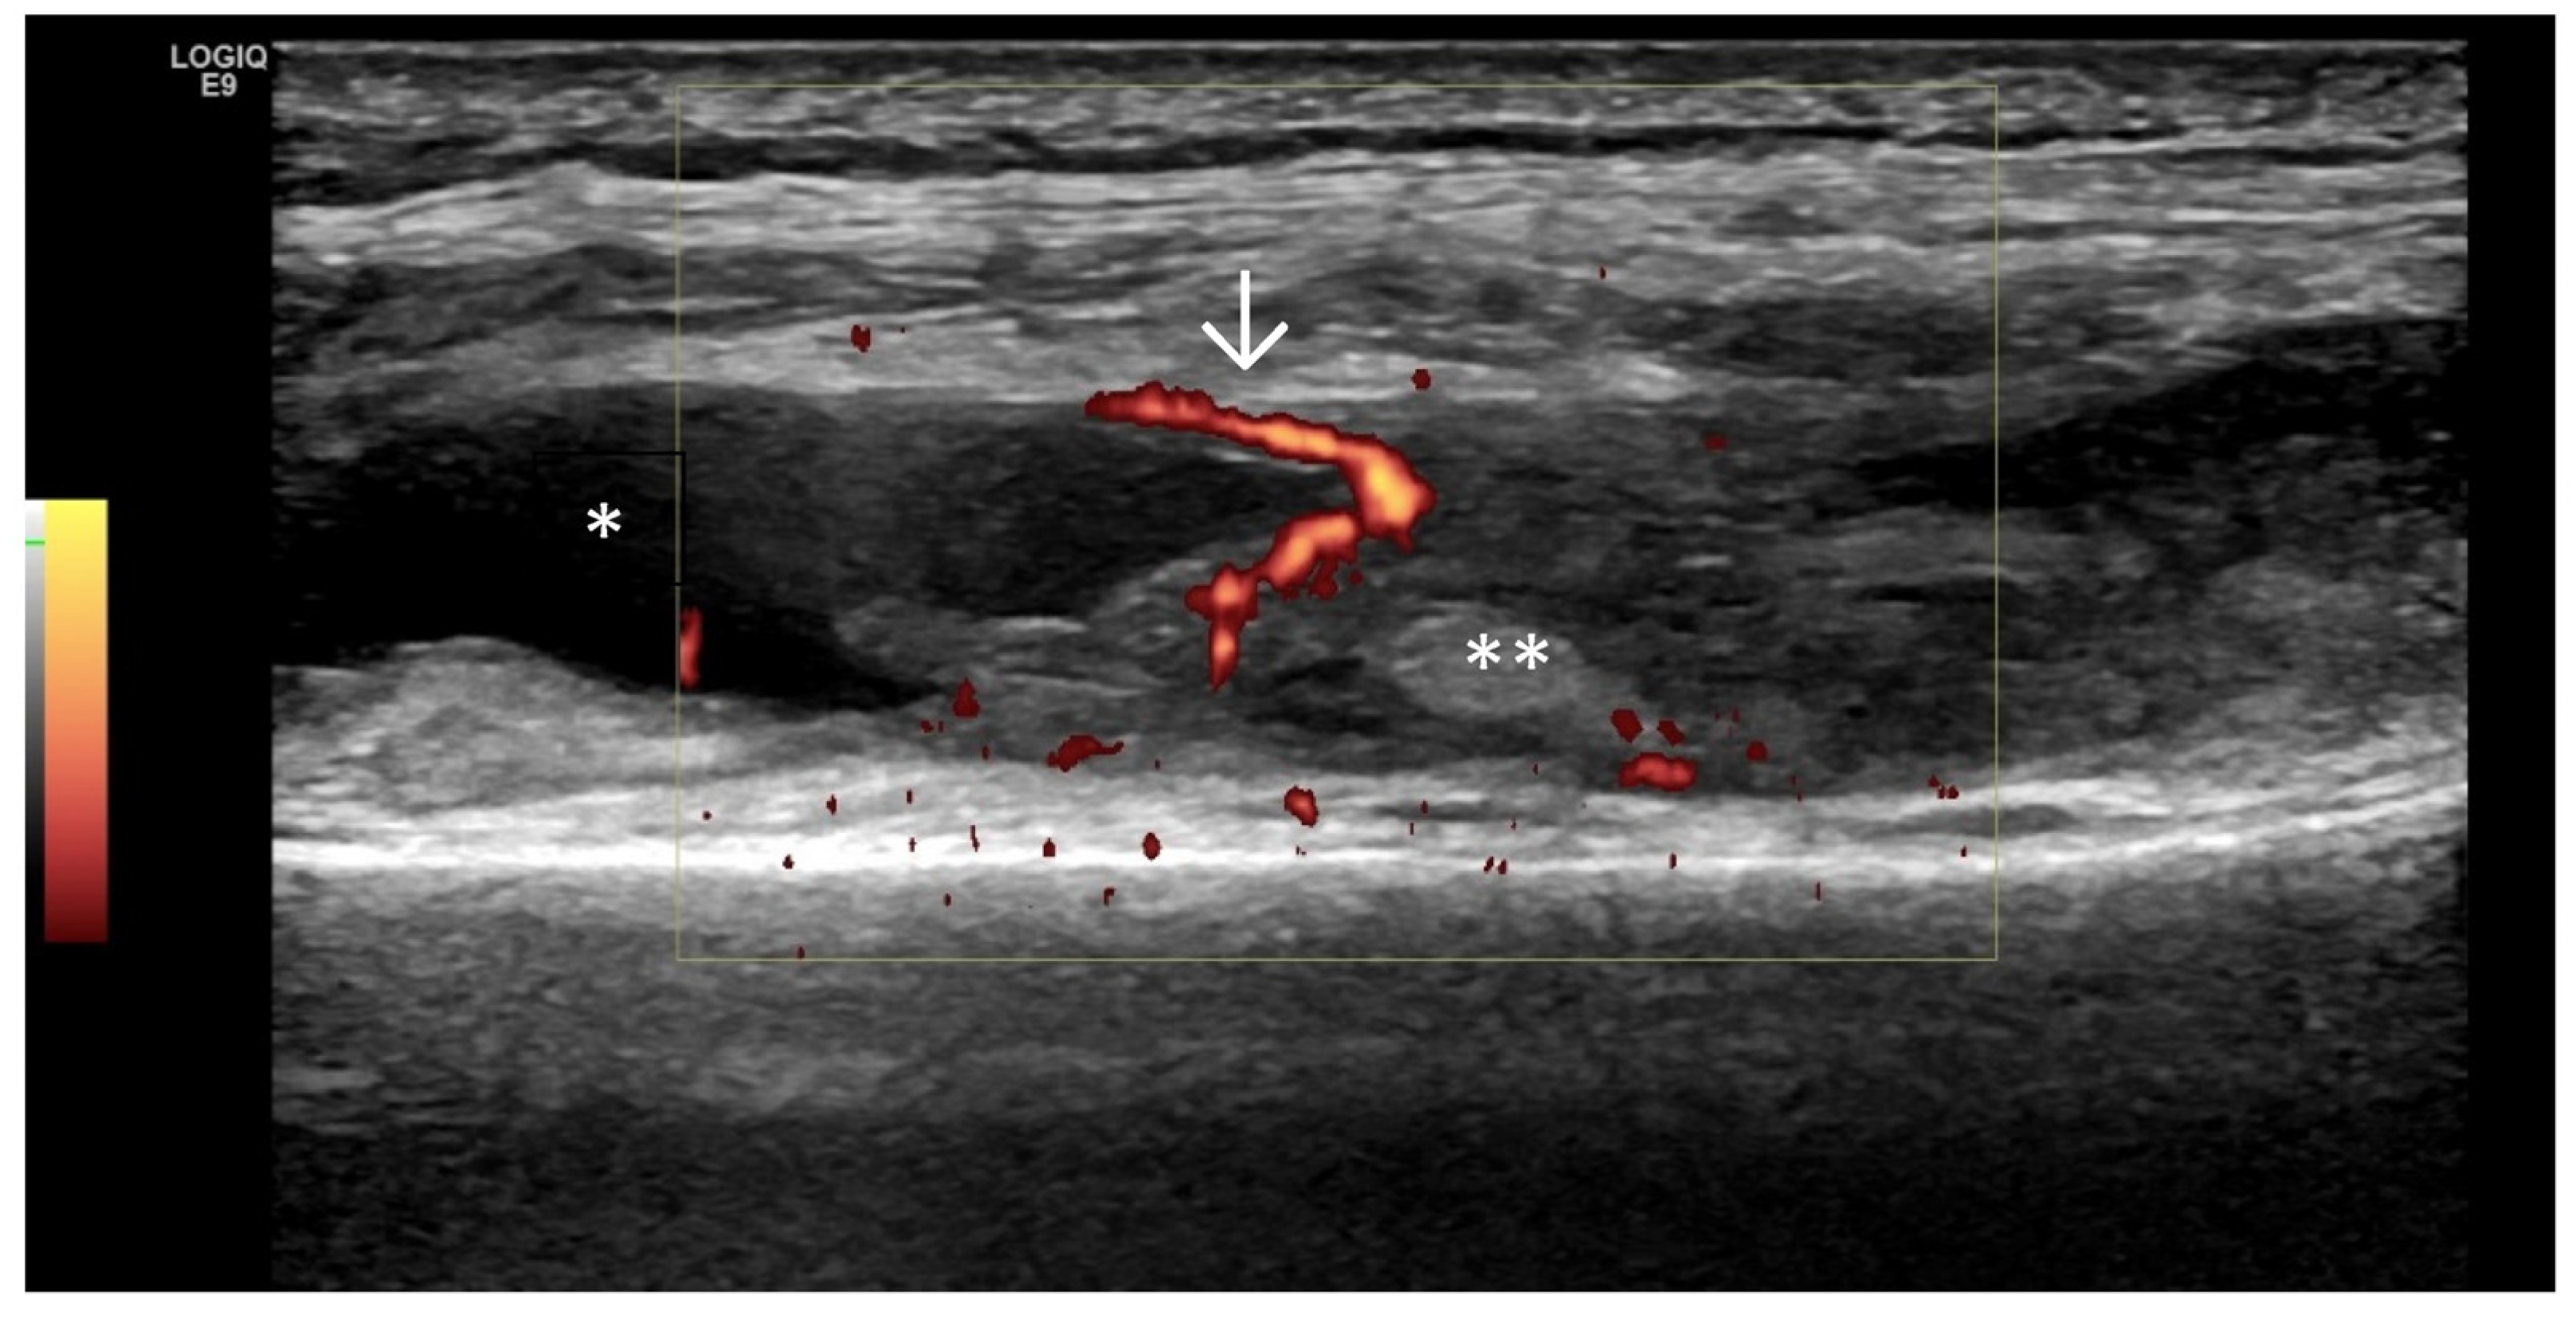

- Predominant synovial proliferation, fat pads, and Hoffa synovitis (with a small amount of intra-articular effusion);

4. Examples of US Phenotypes